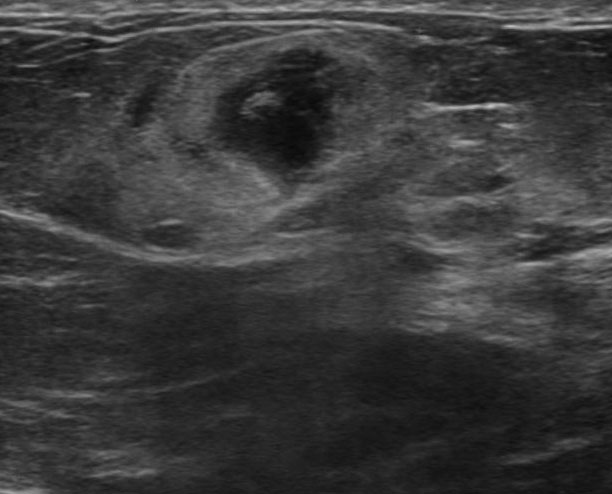

The target dataset was developed from 35 breast ultrasound scans that were segmented by an image-processing expert with extensive experience in breast lesion segmentation (the second author). The images, collected from the Web, are of different dimensions, ranging from to pixels (Figure 3, images resized for sake of illustration). These are the same images used to introduce EFIS originally [1].

Ultrasound images are generally difficult to segment, primarily due to the presence of speckle noise and low level of local contrast. It should be noted that the segmentation of ultrasound actually does require a complete processing chain, (including proper preprocessing and post-processing steps). However, the purpose of using these images was solely to demonstrate that the accuracy of the segmentation can be increased with the application of SC-EFIS.